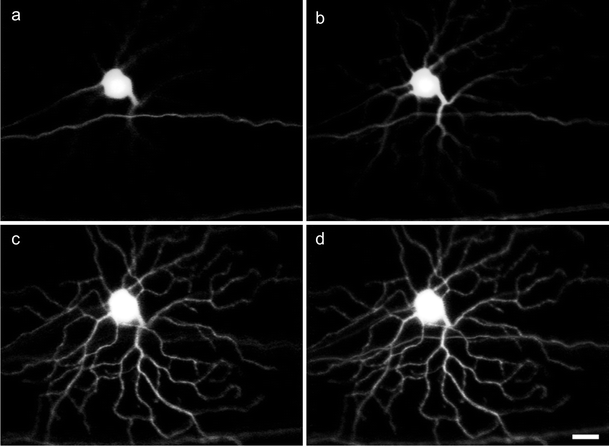

In vivo fluorescence images of a ganglion cell expressing fluorescence protein obtained by using an adaptive optics confocal laser scanning instrument. a–c Images obtained from three focal planes. d Maximum intensity projection image generated from five separate focal planes. Bar 20 μm. Adapted with permission from Biomed Opt Express (Geng et al. 2012)